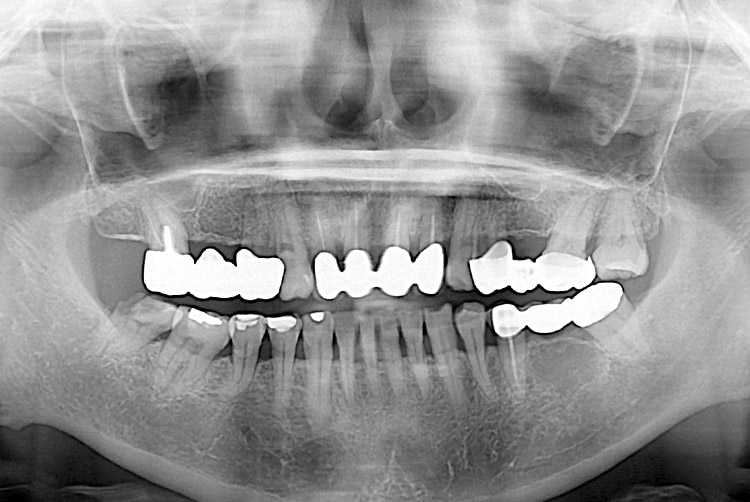

[임플란트] 임플란트

치료후 : 2022-12-15

세종치과는 많은 환자와 다양한 케이스를 바탕으로 항상 편안한 임플란트 수술을 제공하고자 노력하고,

오래동안 튼튼히 쓸 수 있는 임플란트 수술을 가장 큰 목표로 삼고 있습니다.